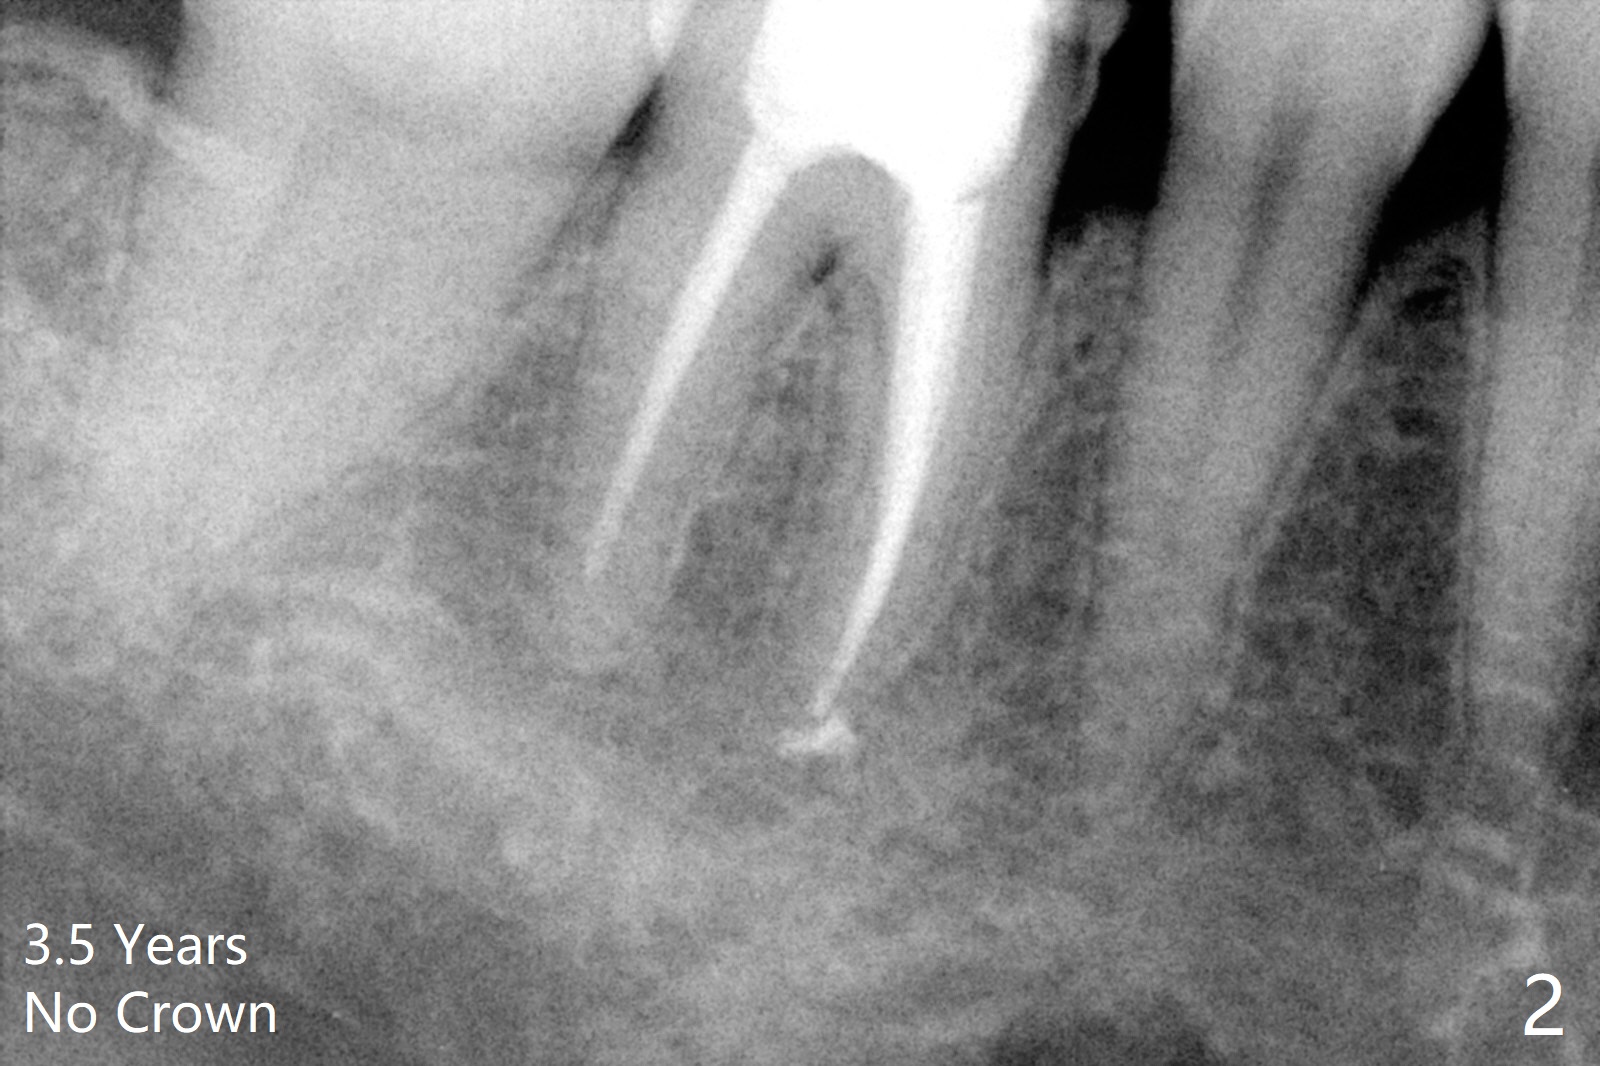

A 47-year-old woman with one carious tooth in her mouth (at #30) received RCT 14 years ago (Fig.1). The molar survives without crown for 3.5 years (Fig.2) and with crown for 8 years (Fig.3). The tooth has 2nd decays 10 years post crown (14 years post RCT, Fig.4 *). The crown dislodges 2 months later (Fig.5). Does the crown inadvertently reduce the longevity of the tooth simply hampering oral hygiene? After osteotomy until 4.5x10 or 13 mm IS drill with guide and 5 mm Bicon reamer free hand, place either 5x6 or 11 mm Bicon implant (Fig.6). Keep the black insertion plug to hold periodontal dressing or a provisional, which will be bonded to the neighboring tooth. Prepare PRFx1 for sticky bone around the not-so-stable implant. A 5x11.5 mm bone-level implant is planned by CT (Fig.7). Socket shield will be conducted to reduce buccal plate collapse. If the osteotomy depth is 10 mm due to limited mouth opening, place 4.5x6 mm Bicon implant. Otherwise 4.5x8 mm one. Return to Lower Molar Immediate Implant, Prevent Molar Periimplantitis (Protocols, Table), Trajectory II, Metronidazole Early Intervention Xin Wei, DDS, PhD, MS 1st edition 09/01/2019, last revision 11/10/2019